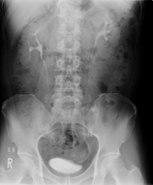

DIP(点滴静脈性腎盂造影)とは

造影剤を点滴静注し、腎臓、尿管、膀胱の形態的変化を10分・20分・30分で撮影し尿管の閉塞などが明瞭になります。

10分 20分 30分

また、膀胱像の大きさ(萎縮)、肉柱形成(神経因性膀胱)、偏位(周囲からの圧迫)、陰影欠損(腫瘍、尿管癌)などについて観察します。